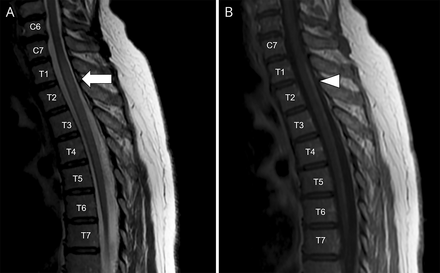

改变表面和深部感觉下肢与轻快的下肢深部腱反射和括约肌障碍本地化脊髓的赤字。没有力量的赤字进一步表明主要的后定位病变。脊髓的核磁共振显示2 T2 / fluid-attenuated反转恢复hyperintense,中央髓病变,从C2 C4和从C7到T7 (图,一个)。Postgadolinium T1序列显示薄,纵广泛,单纯对比度增强(CE)在C2-C3 T1-T6级别(图B)。脑MRI是不起眼的。脑脊液检查显示,蛋白质浓度轻微海拔(68 mg / dL,正常范围- 40 mg / dL),与正常的葡萄糖和没有细胞。血细胞计数、肝酶,血清肌酐,甲状腺功能正常范围内。

(一)脊髓MRI显示,在矢状T2序列,hyperintense,中央髓损伤,延长从C7到T7(箭头所指)。(B) Postgadolinium T1序列显示薄,纵广泛,单纯对比度增强T1 T6水平(箭头)。